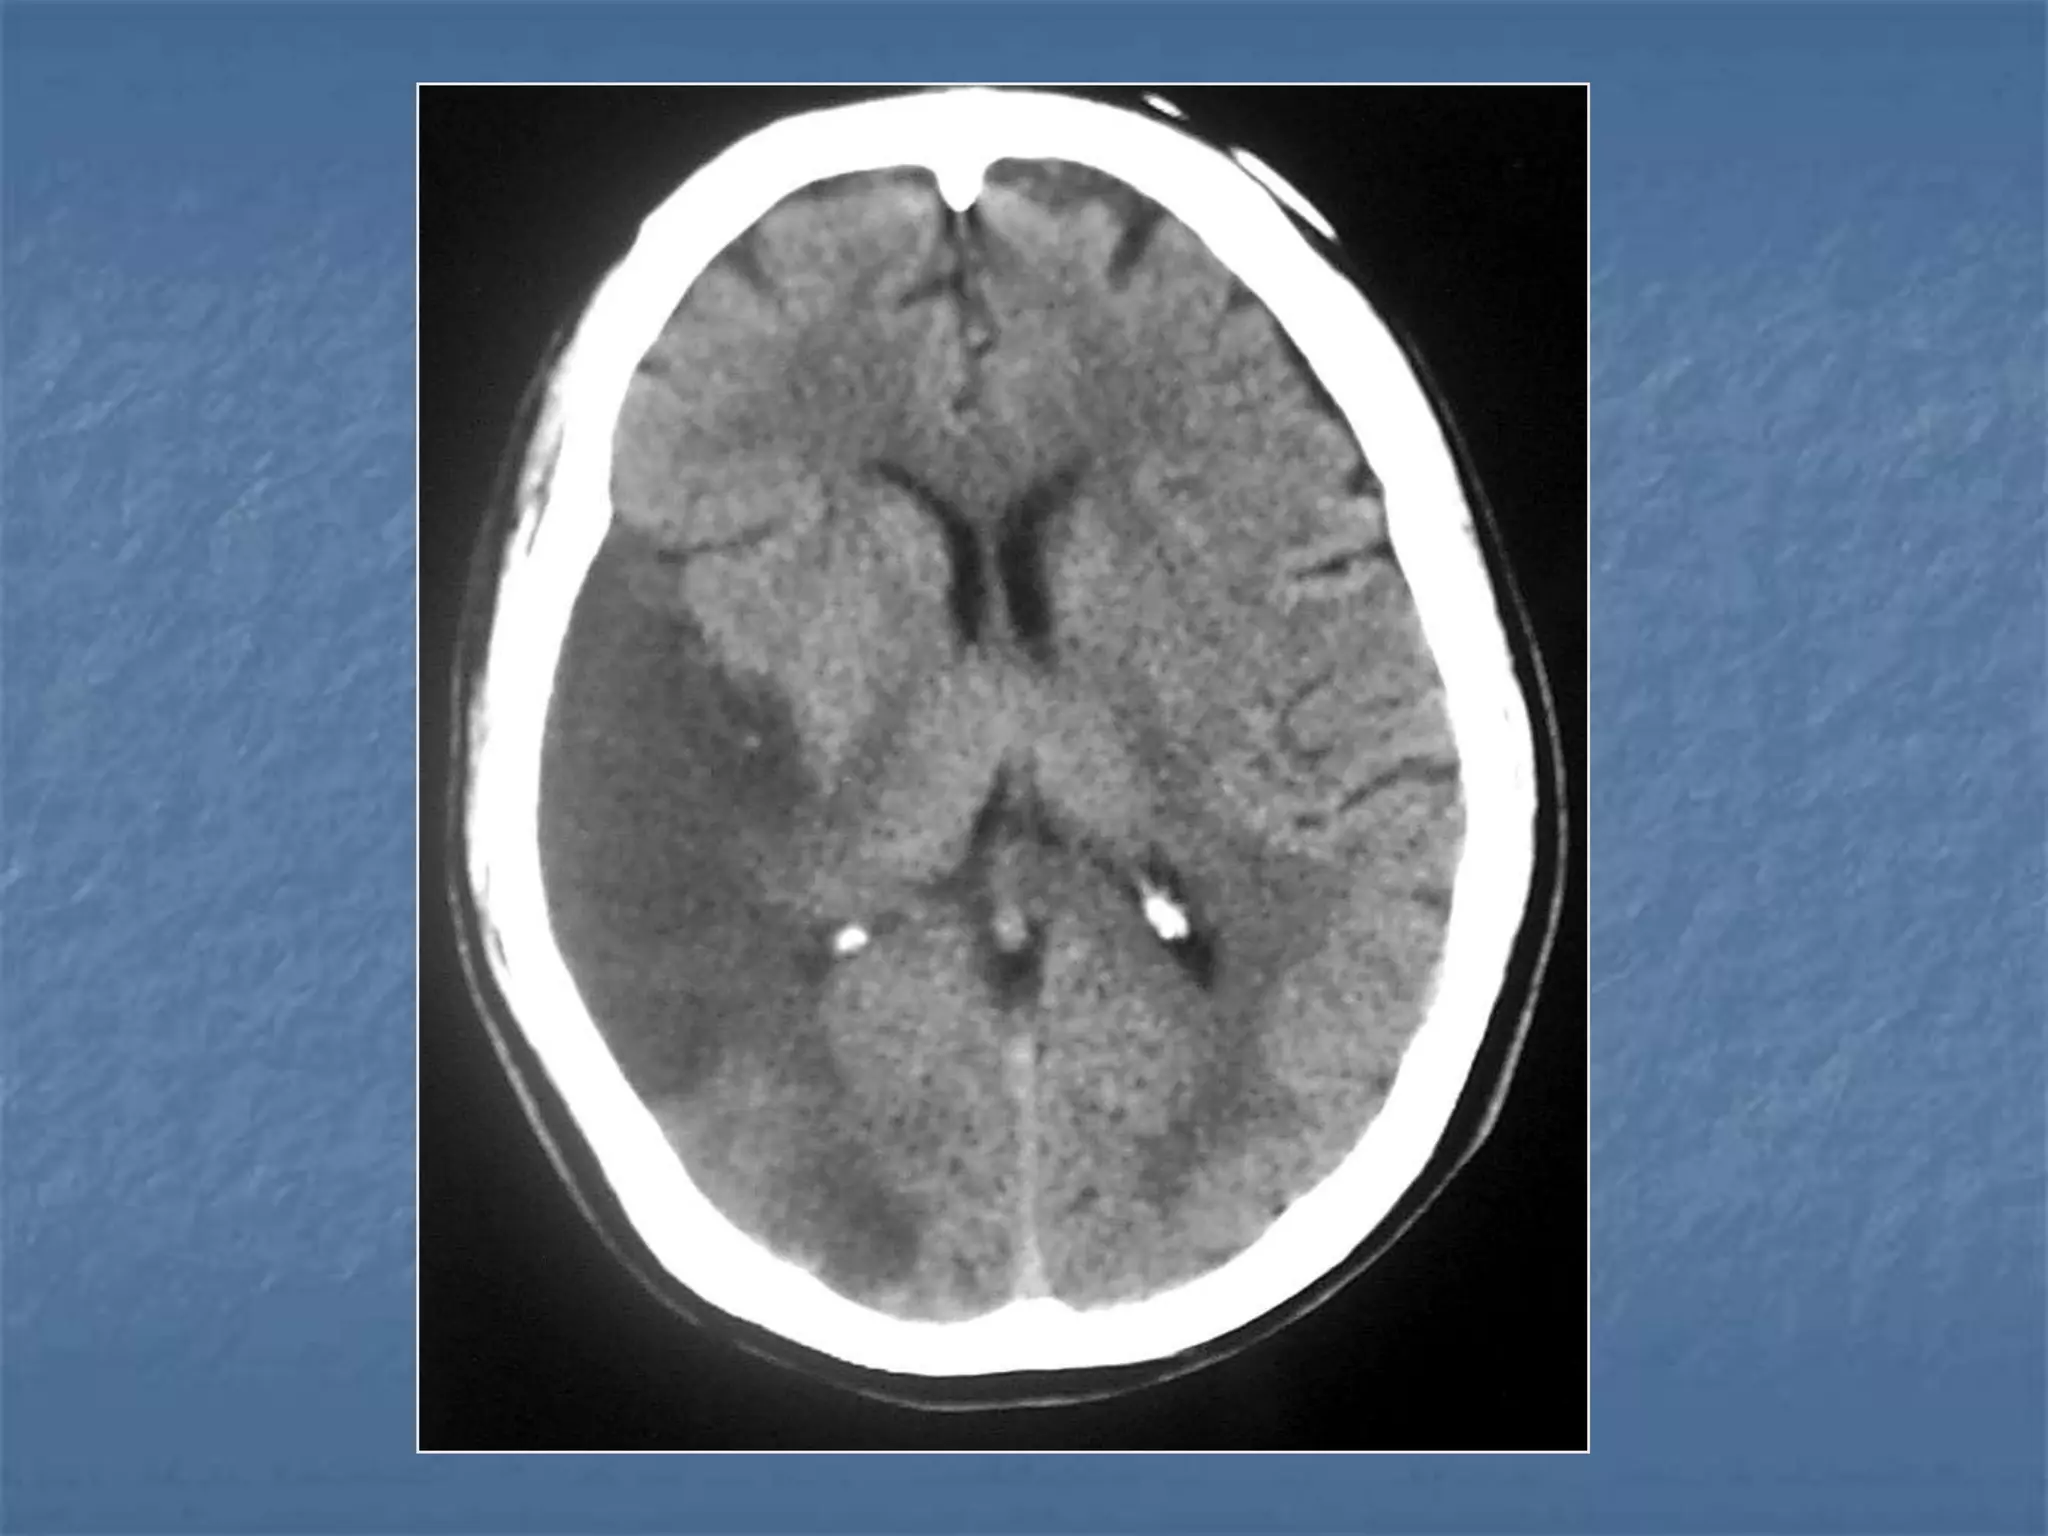

Hypertensive Hemorrhage

 Hypertensive hemorrhage accounts for

approximately 70-90% of non-traumatic primary

intracerebral hemorrhages. It is commonly due to

vasculopathy involving deep penetrating arteries

of the brain. Hypertensive hemorrhage has a

predilection for deep structures including the

thalamus, pons, cerebellum, and basal ganglia,

particularly the putamen and external capsule.

Thus, it often appears as a high-density

hemorrhage in the region of the basal ganglia.

Blood may extend into the ventricular system.

Intraventricular extension of the hematoma is

associated with a poor prognosis.

Haemorrhagic StrokeEtiology

 Hypertension

 Vascular malformation

 Aneurysm

 Trauma

 Amyloid angiopathy

 Tumor

 Coagulopathy

 Hemorrhages can occur in the intraparenchymal,

subarachnoid, intraventricular, subdural and

extradural spaces.

 Location of hypertensive hemorrhage:

Putamen, external capsule, thalamus, pons,

cerebellum, subcortical white matter